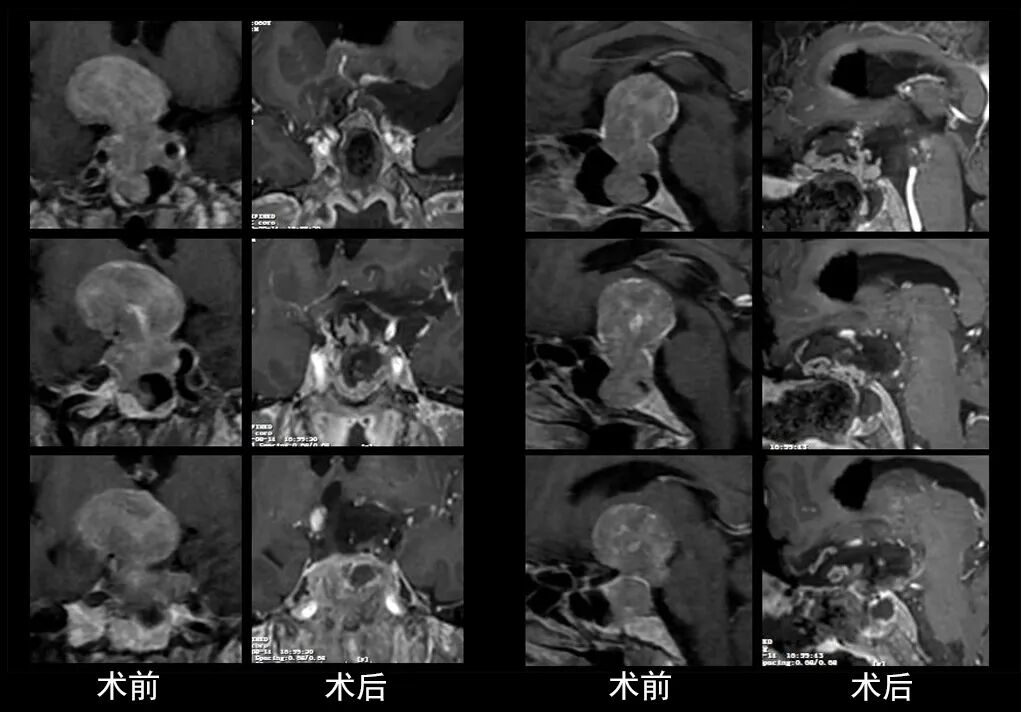

本研究中采用联合手术策略的代表性病例展示:

case 1

case 2